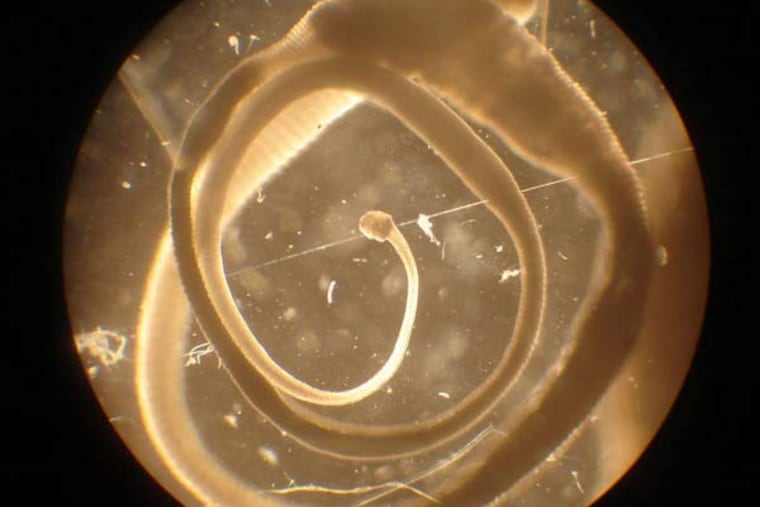

Helminthic therapy is an experimental type of immunotherapy that involves ingesting worm-like parasites or their eggs in pill form. It has been used as an alternative treatment for allergies, asthma, autism, Crohn’s disease, multiple sclerosis, Sjogren’s syndrome, and ulcerative colitis.

Proponents of the therapy say that as our hygiene and living conditions improved, we have been exposed to fewer microbes and infectious agents, which has led to increases in autoimmune and inflammatory diseases.

There have been a limited number of clinical trials involving helminthic therapy, and all but one were outside the U.S. The therapy does not have FDA approval.